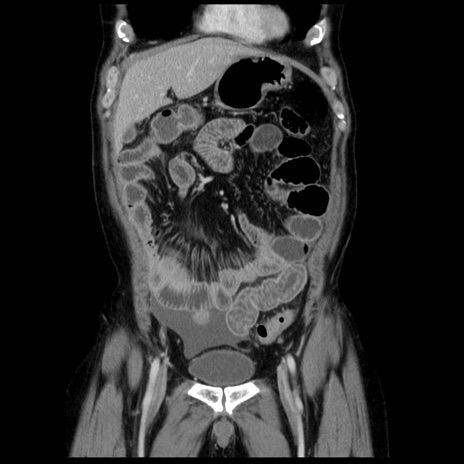

横断像

【症例】40歳代男性

【現病歴】2日前から胃痛あり。徐々に周期的な激痛に変化した。本日になっても激痛があるため受診。

【身体所見】意識清明、BT 38-39℃台あり、腹部:膨満、やや硬、右下腹部に圧痛あり。

【データ】WBC 8500、CRP 23.26